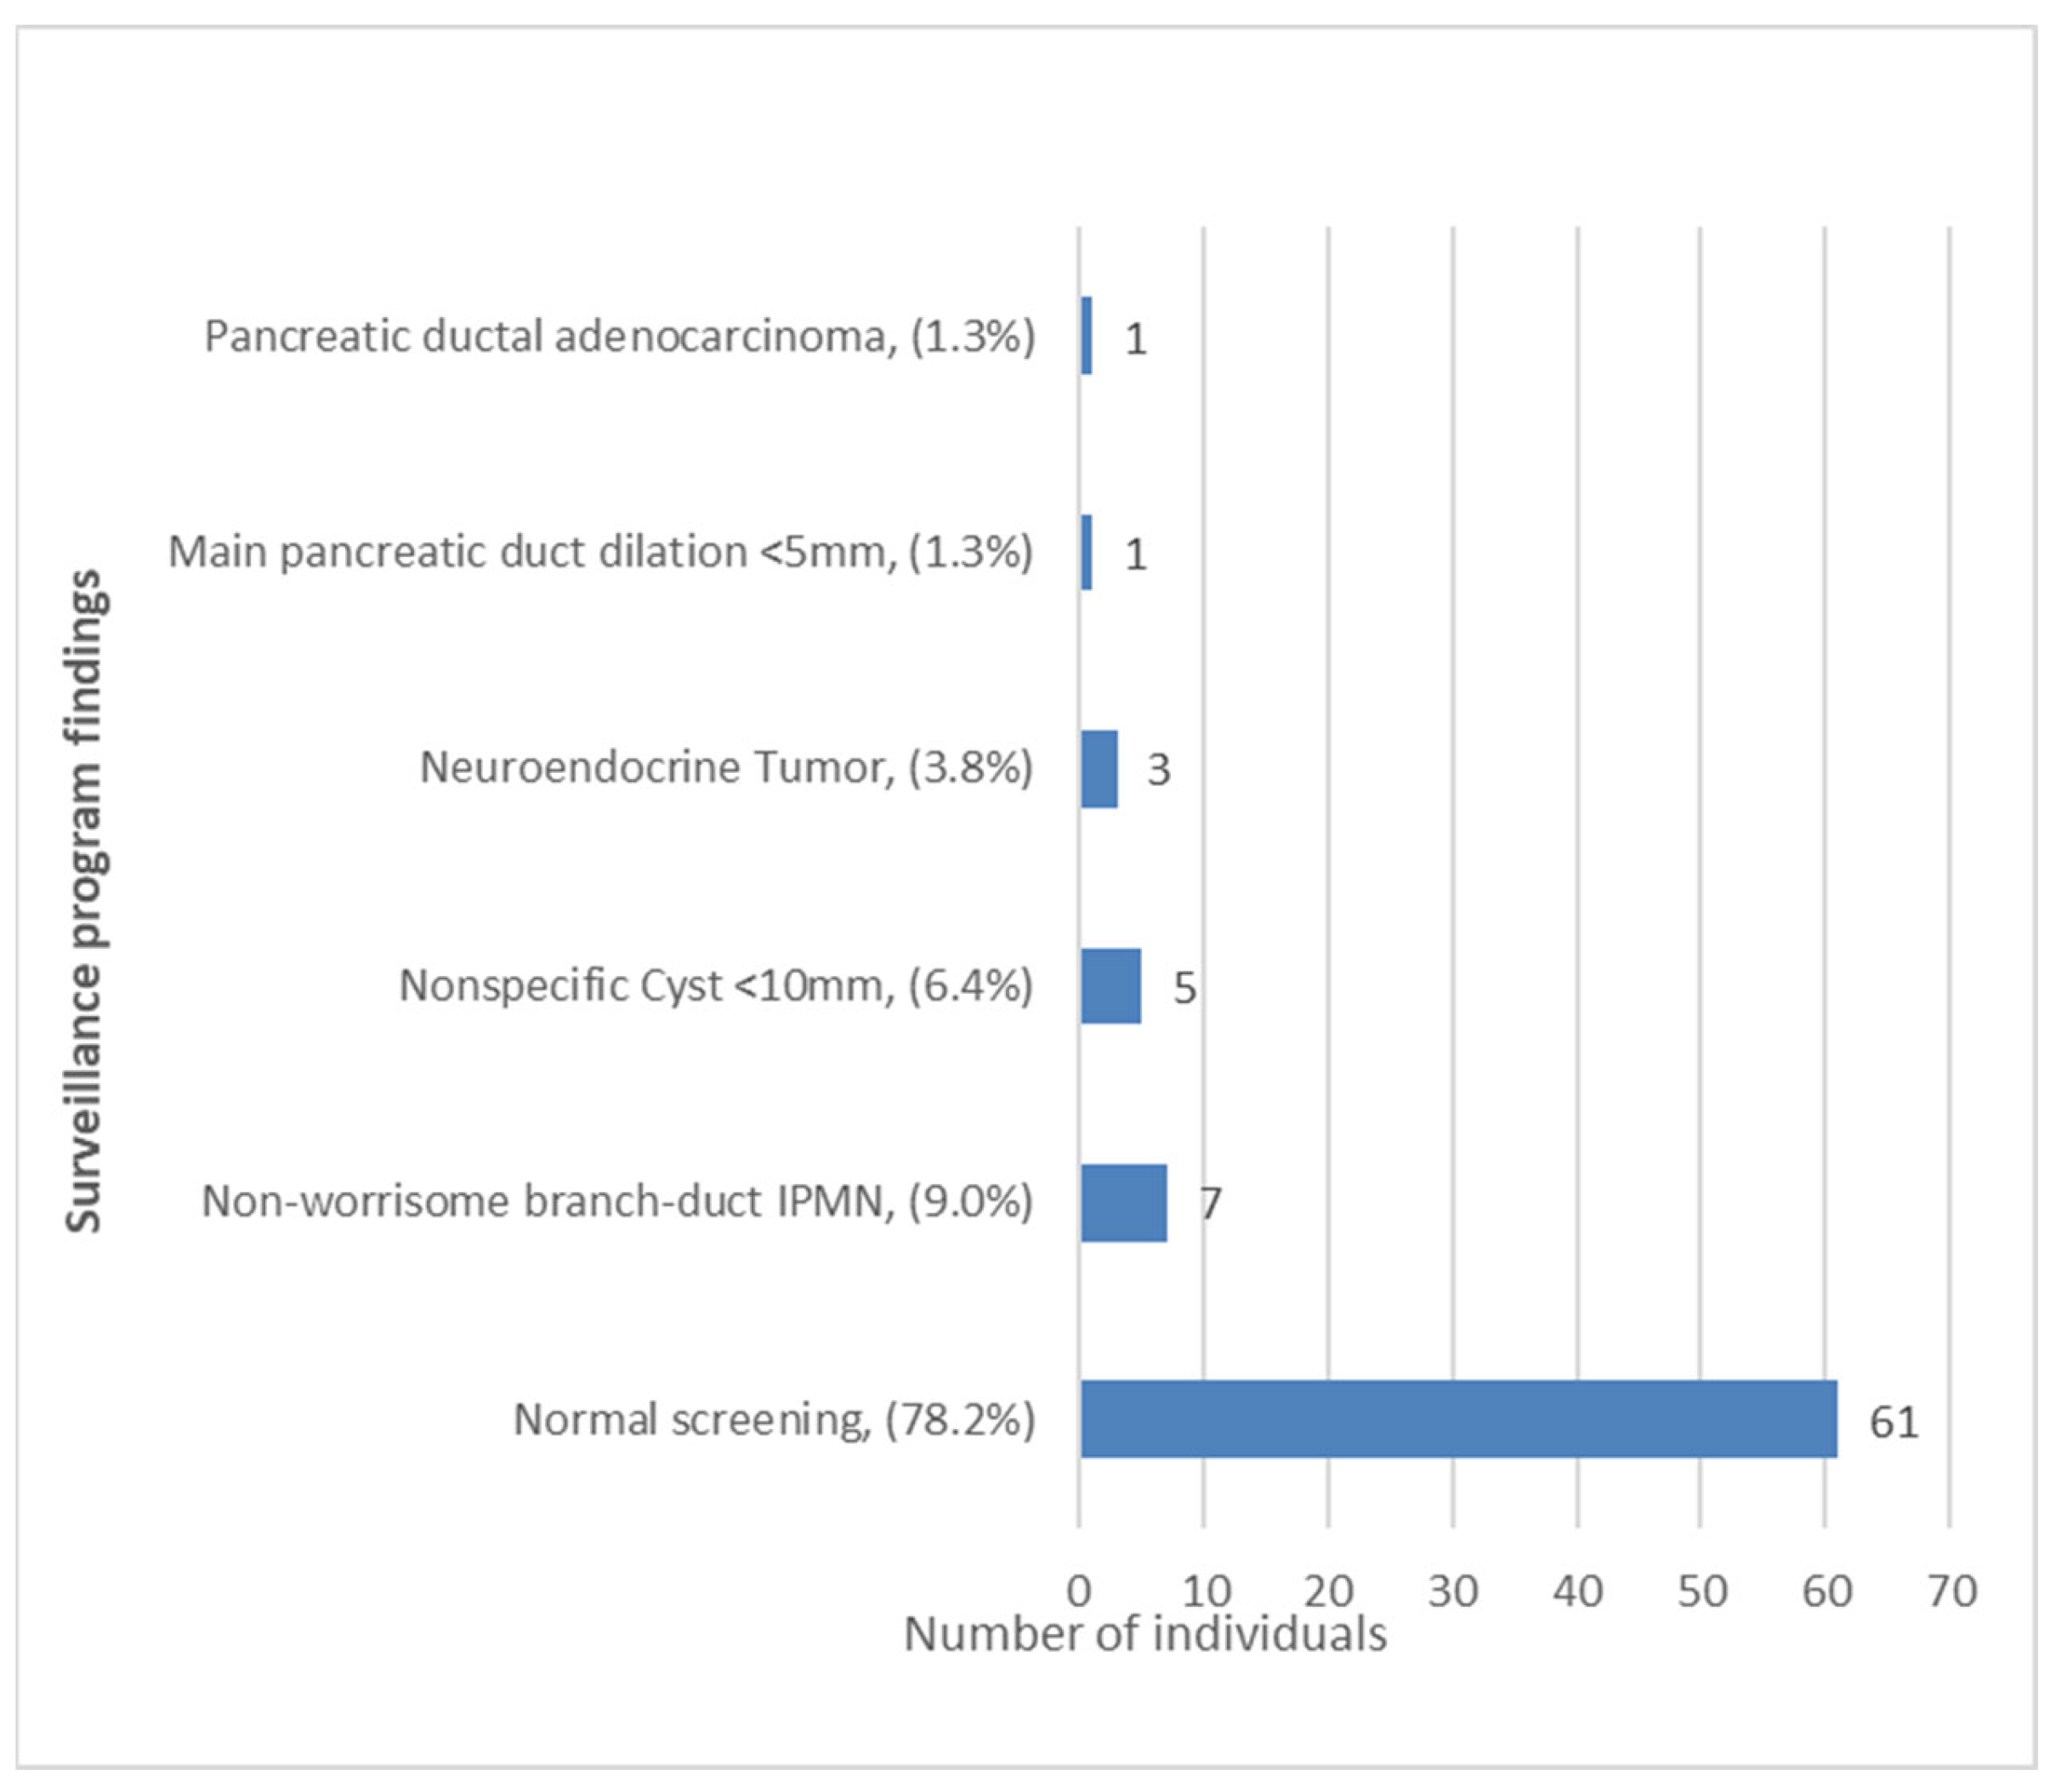

3.2. Pancreatic Cancer Surveillance Program: Characteristics and Findings

| Lesions Detected at the Surveillance Program (n = 17) | Test Performed During Follow-Up | Test that Detected the Lesion | ||

|---|---|---|---|---|

| EUS | MRI | EUS | MRI | |

| Main pancreatic duct dilation (5 mm) | Yes | Yes | Yes | No |

| IPMN | Yes | Yes | Yes | Yes |

| IPMN | Yes | Yes | Yes | Yes |

| IPMN | No | Yes | Not performed | Yes |

| IPMN | Yes | No | Yes | Not performed |

| IPMN | Yes | No | Yes | Not performed |

| IPMN | Yes | Yes | Yes | Yes |

| IPMN | Yes | Yes | Yes | No |

| Neuroendocrine tumor | Yes | Yes | Yes | No |

| Neuroendocrine tumor | Yes | Yes | Yes | Yes |

| Neuroendocrine tumor | Yes | Yes | Yes | Yes |

| Pancreatic cancer | Yes | No | Yes | Not performed |

| Nonspecific cyst | Yes | Yes | Yes | No |

| Nonspecific cyst | Yes | No | Yes | Not performed |

| Nonspecific cyst | Yes | Yes | Yes | Yes |

| Nonspecific cyst | Yes | No | Yes | Not performed |

| Nonspecific cyst | Yes | No | Yes | Not performed |